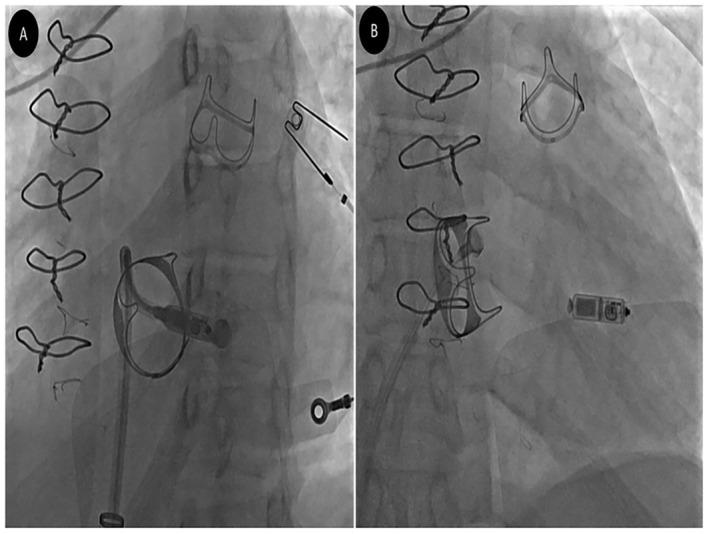

A 21-year-old man, known case of the repaired congenital heart disease, developed complete atrioventricular block (AVB) one week after simultaneous bioprosthetic pulmonary and tricuspid valve replacement and atrial septal defect repair. Considering the persistence of the AVB, it was decided to implant a permanent pacemaker. After considering all available options and the issues related to the patient, it was decided to implant a leadless pacemaker (LLP). A Micra pacemaker was implanted successfully, and the patient was discharged in good condition and without any complications. Follow-up evaluation showed appropriate LLP and bioprosthetic valve functioning. Limited prior experiences and the present report showed that LLP appears to be an ideal option in the patients with bioprosthetic tricuspid valve complicated by conduction disorders.

一名21岁男性,为先天性心脏病修复术后患者,在同期进行生物瓣肺动脉瓣和三尖瓣置换及房间隔缺损修复术后一周出现完全性房室传导阻滞(AVB)。考虑到房室传导阻滞持续存在,决定植入永久性起搏器。在考虑了所有可用选项及与患者相关的问题后,决定植入无导线起搏器(LLP)。成功植入了美敦力Micra无导线起搏器,患者出院时情况良好,无任何并发症。随访评估显示无导线起搏器及生物瓣功能正常。既往有限的经验及本报告表明,对于合并传导障碍的生物瓣三尖瓣患者,无导线起搏器似乎是一个理想的选择。